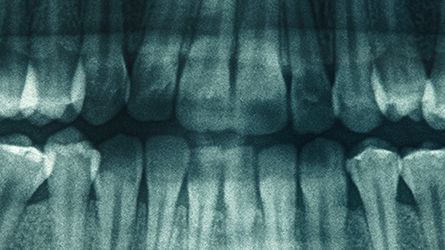

Hamilton NJ-Dental Implants

Dental Implants Offered by Our Hamilton Dental Implant Specialists: